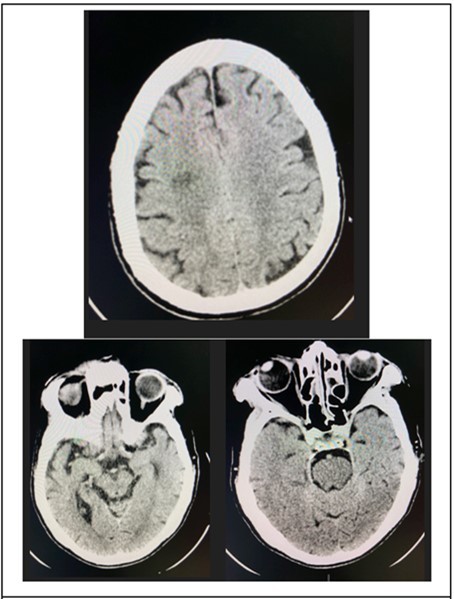

At the emergency room of the tertiary hospital, the patient had persistence of the diplopia and dizziness. The initial impression at that time was Cerebrovascular Infarct, thus a Plain Cranial CT Scan was done (conducted 6 hours after the onset of symptoms), which revealed a hypodense focus in the sub-cortical region of the right centrum semiovale extending to the right corona radiata, orbits, midbrain and pons were all normal. (Figure 2 and Figure 3)

Figure 5.Cranial CT Scan plain, axial with orbital cuts of the patient which shows un remarkable orbit, midbrain and pons findings.

Cranial MRI plain and with contrast was requested by the ophthalmology service to further investigate on the brainstem. The subsequent study done 21 days after onset of symptoms, revealed patchy bright flair signals were noted in the subcortical white matter and periventricular area. (Figure 6) The orbits, midbrain, pons were regarded as unremarkable.